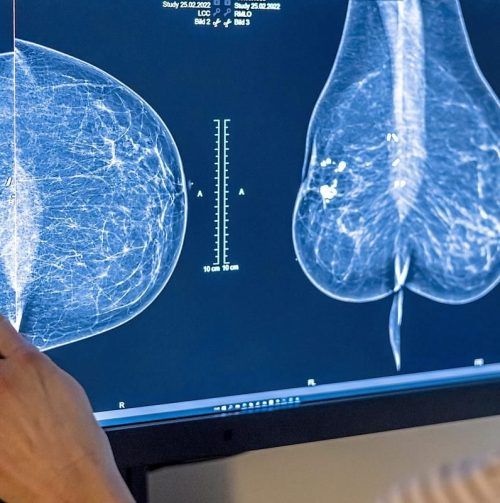

Brustkrebs: Mammografie kann Leben retten. © dpa